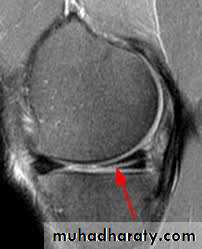

Meniscus injury

Meniscus injury are common in young adult especially football players, result froma twisting of semi-flexed or flexed knee.

The medial meniscus torn more than lateral meniscus.

The tear might affect the anterior or posterior horn of meniscus

as pedunculated tag ,or as bucket handle, sometimes

horizontal tears

or degeneration might occur.

Patients give

history of trauma,pain,

inability to extend knee

and delayed swelling of knee.

Locking

(in ability to fully extend the knee).

and unlocking are common feature of meniscus injury .

Diagnosis of meniscus

injury depend on

classical history

and clinical finding

ByMcmurray test.

MRI

is reliable method of diagnosis,

Arthroscopycan be used to confirm the diagnosis.

.Treatment

of choice is to remove the teared segment of meniscus arthroscopically.